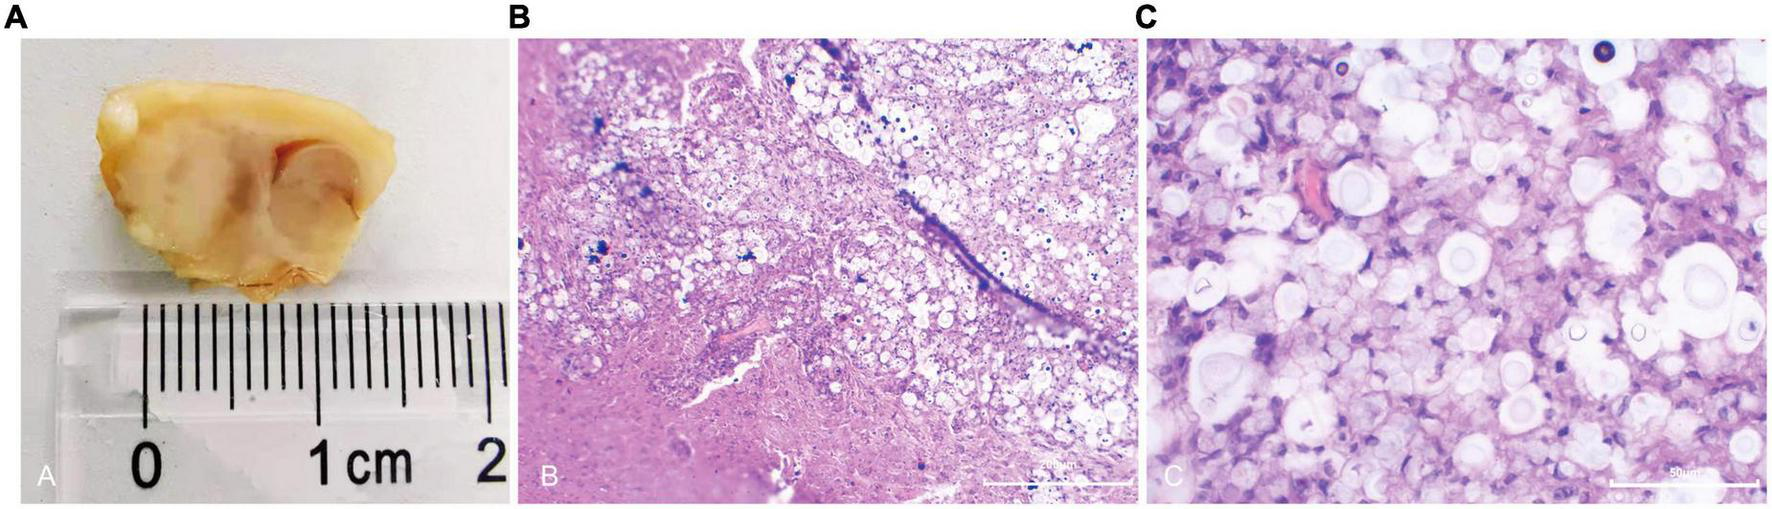

Pathological findings

Brain biopsy of rats with cryptococcal granuloma showed thick yellow exudates, and necrotic foci can be seen in the caudate nucleus and part of the brain surface. Granuloma foci composed of lymphocytes and multinucleated giant cells can be seen under the microscope, with many cryptococci neoformans (Figure 4). Some rats’ ipsilateral meninges and ependyma were thickened to varying degrees, and Cryptococcus neoformans infiltrated some thickened areas.

FIGURE 4

General and microscopic pathological observations of cryptococcal granuloma of the brain. In macroscopic view (A), a mass necrotic focus can be seen in the caudate nucleus area with thick exudate on the surface; under 10 × 10-fold microscope (B) with HE staining, multiple cysts and inflammatory cell infiltration in brain parenchyma were seen; under the 40 × 10-fold microscope (C) with HE staining, a large number of circular cryptococci were scattered in the brain parenchyma, and some brain tissues were dissolved.